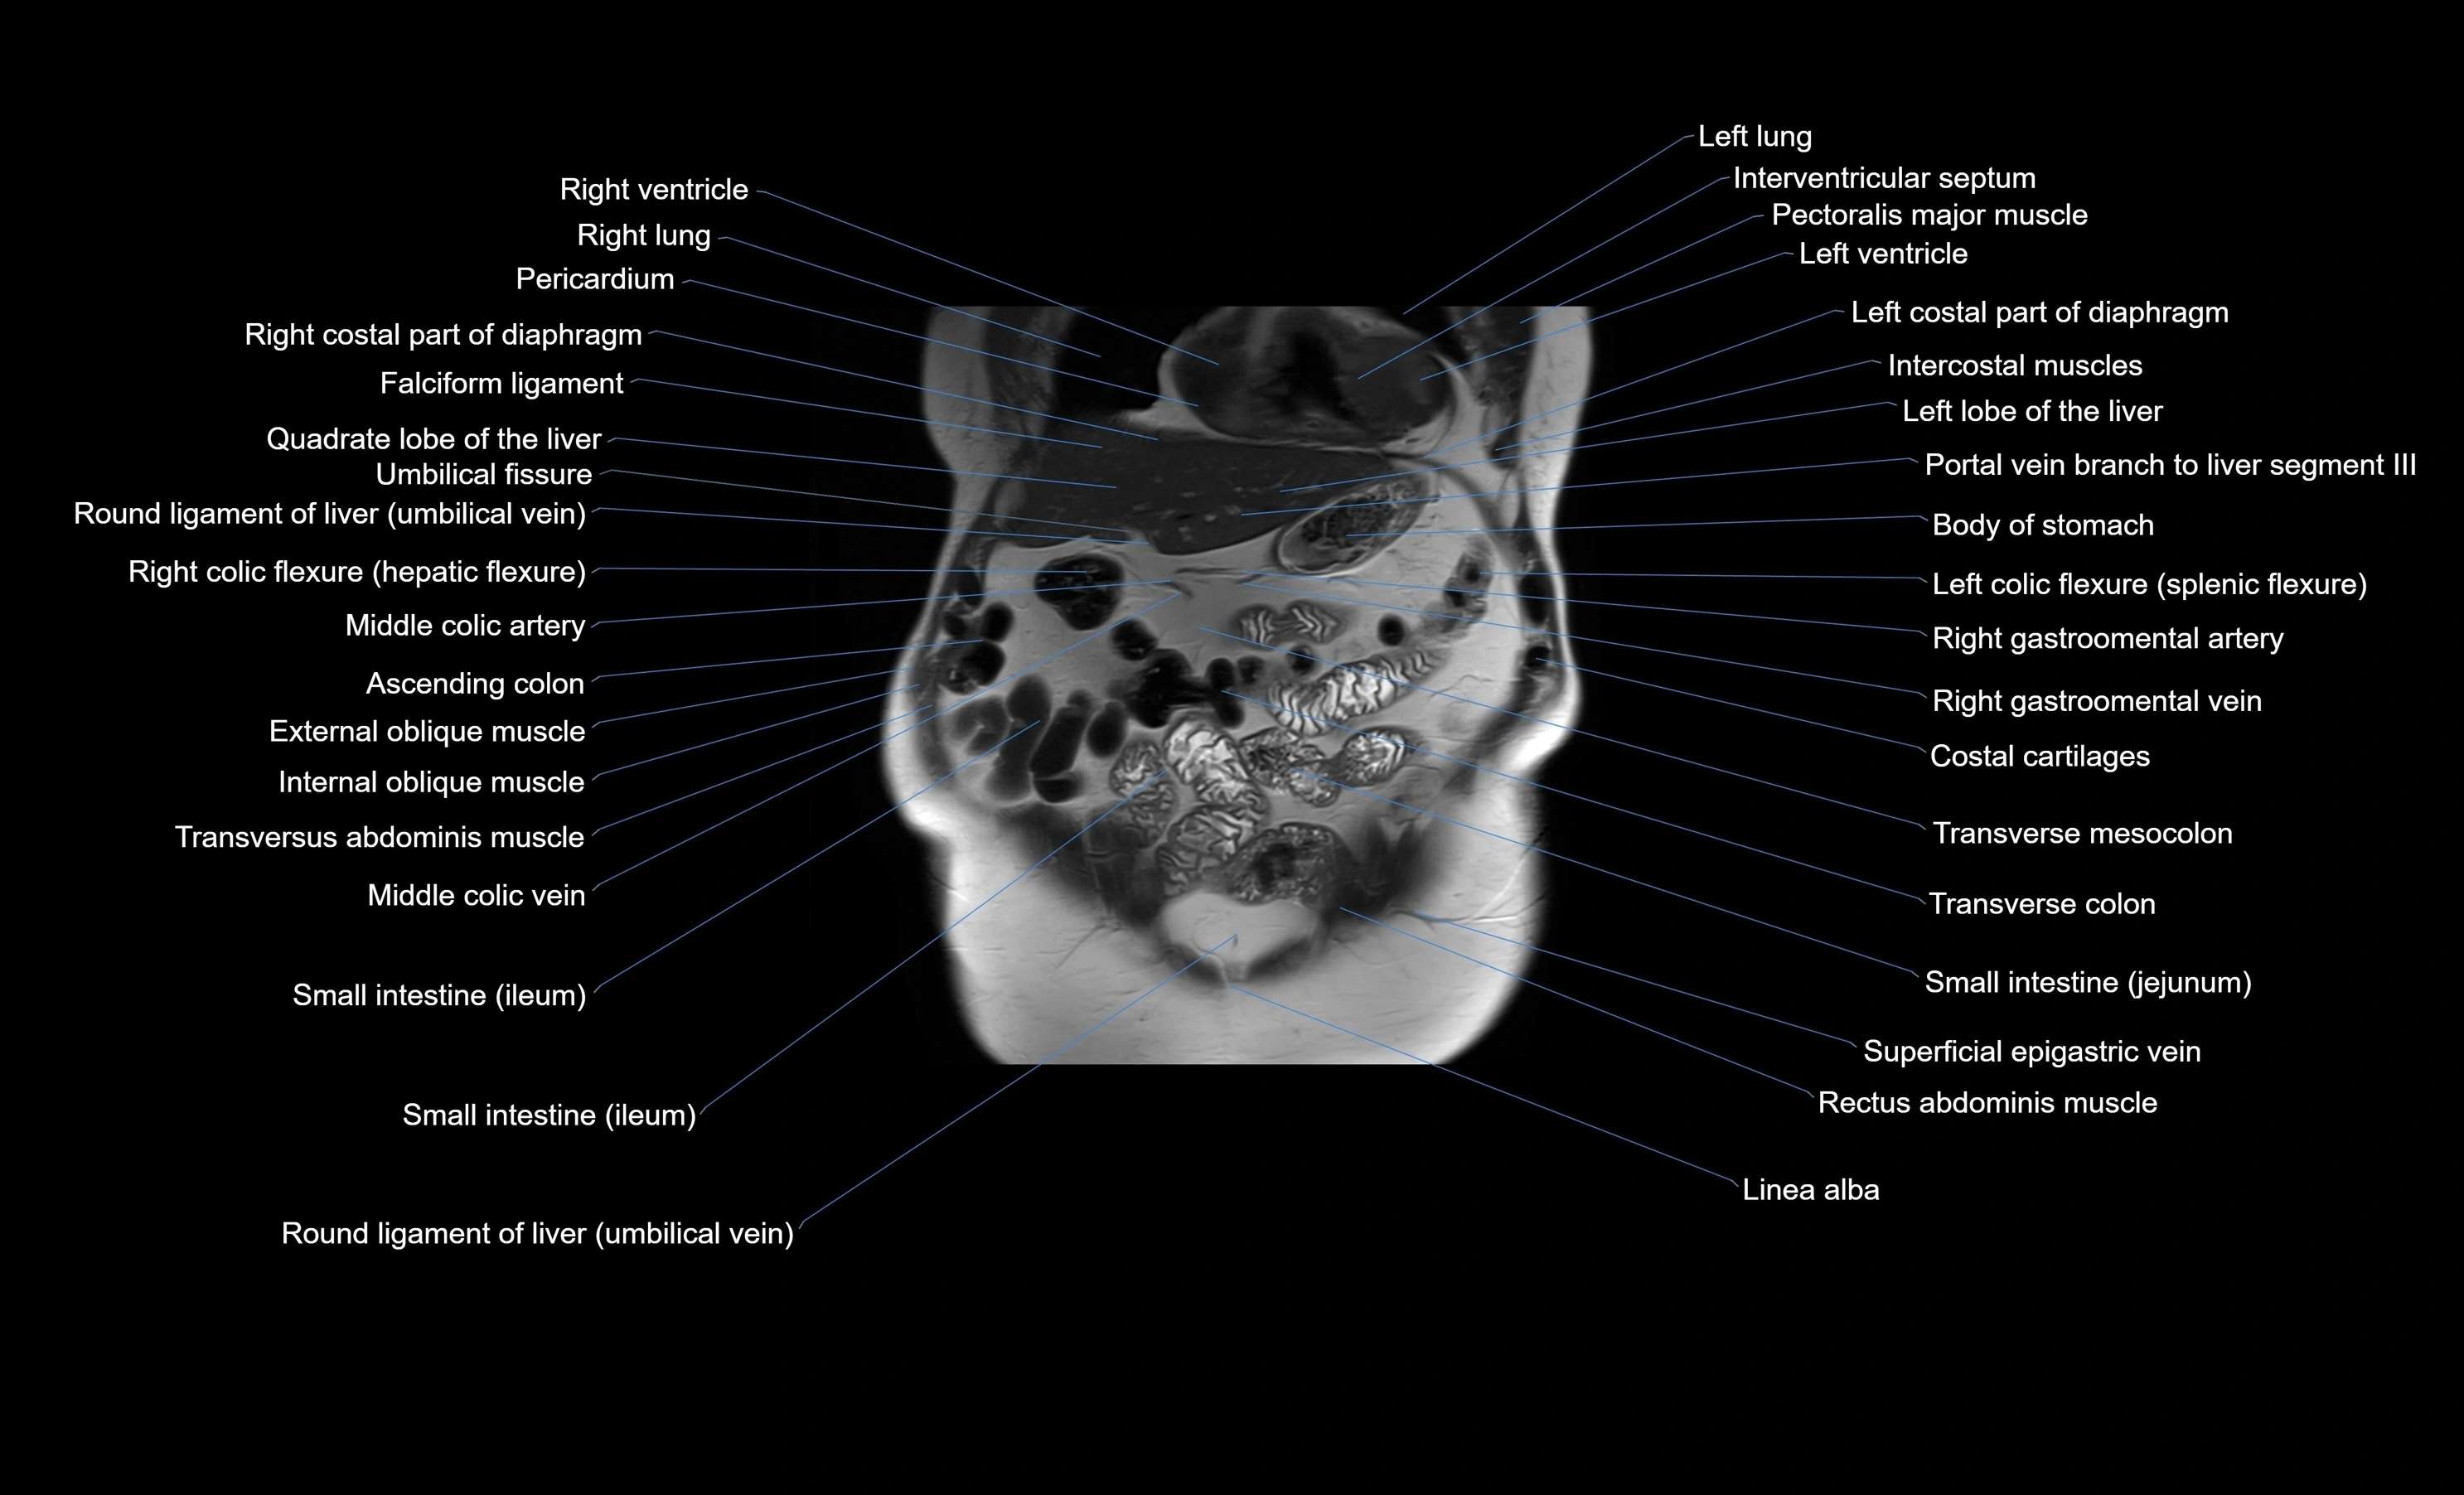

MRI images